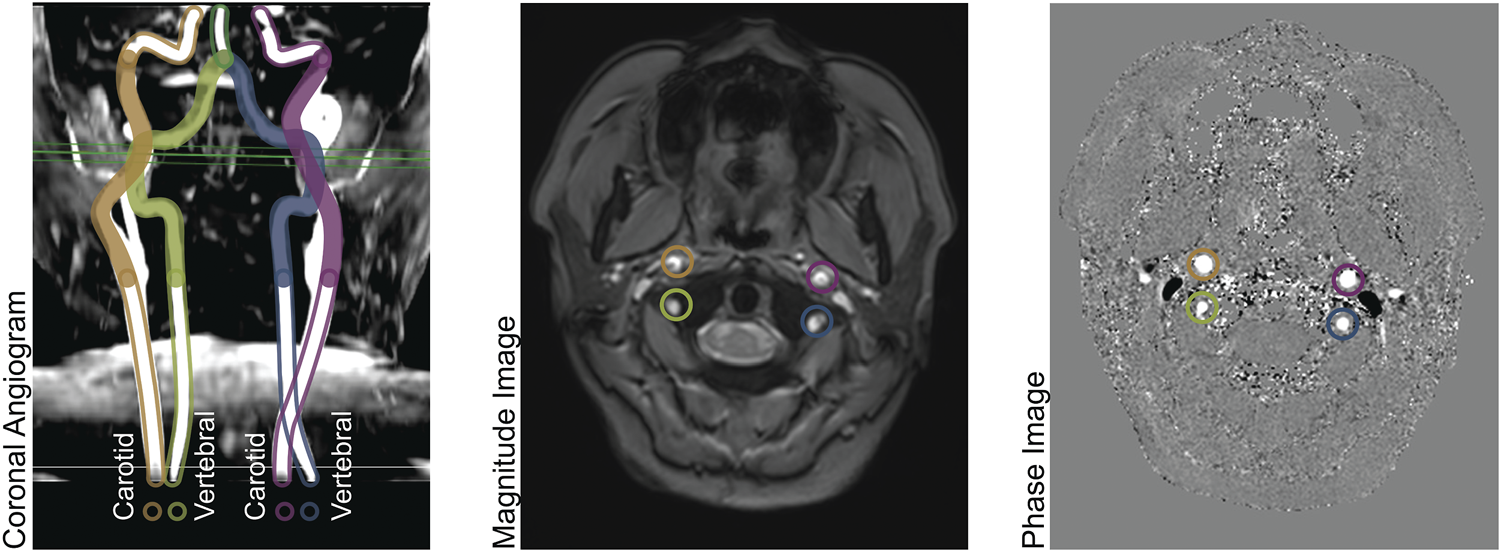

The imaging methods are reported elsewhere in detail and summarized here. (Borzage et al., 2016). We obtained all images with a 3T Philips Achieva and eight-element head coil. A magnetic resonance angiogram localized the vessels in the neck, and a PC MR imaging plane was placed approximately 1 cm above the carotid bifurcation. The angiogram was collected in the axial plane with inline reformatting into sagittal and coronal planes to facilitate orthogonal placement of the PC imaging plane. Image parameters for the PC MR examination were as follows: repetition time, 12.3 ms; echo time, 7.5 ms; field of view, 260 mm; thickness, 5 mm; signal averages, 10; acquisition matrix, 204 × 201; reconstruction matrix, 448 × 448; bandwidth, 244 Hz/pixel; and velocity encoding gradient, 200 cm/s. For this retrospective data analysis, we retained only one PC MR image per patient. Figure 1 demonstrates the coronal angiogram showing the carotid and vertebral arteries together with the magnitude and phase images.

FIGURE 1. Left panel: Coronal Angiogram showing the carotid and vertebral arteries. The solid-colored portion of the vessels are above the bifurcation of the common carotid arteries, and below the level of the basilar artery. The green horizontal plane shows the location of the phase contrast slice. Center panel: a magnitude image; and right panel: a phase image, both acquired at the level indicated in the left panel.